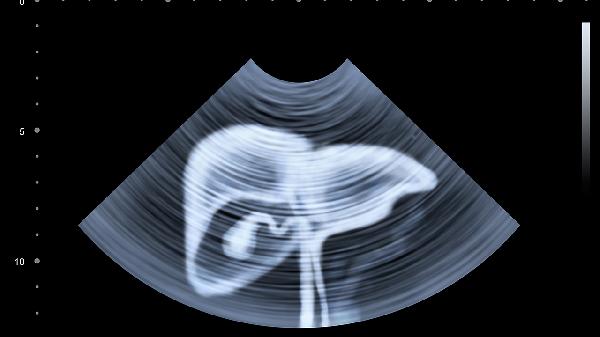

特别提醒:长期饮酒、熬夜、乱吃药的人群,更要留意这些细微变化。肝脏的代偿能力极强,等出现明显腹痛时,往往已经错过最佳干预时机。建议每年做一次肝功能检查和肝脏B超,尤其要关注转氨酶、胆红素、白蛋白这三个关键指标。